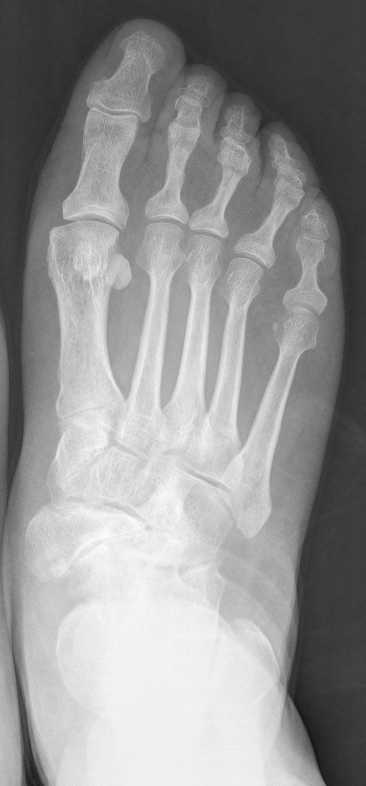

IMÁGENES PREOPERATORIAS, MUESTRAN EL ACORTAMEINTO DE LA COLUMNA MEDIAL POR EL COLAPSO DEL ESCAFOIDES, ASÍ COMO LA FORMA TÍPICA EN COMA EN LA RADIOGRAFÍA ANTEROPOSTERIOR